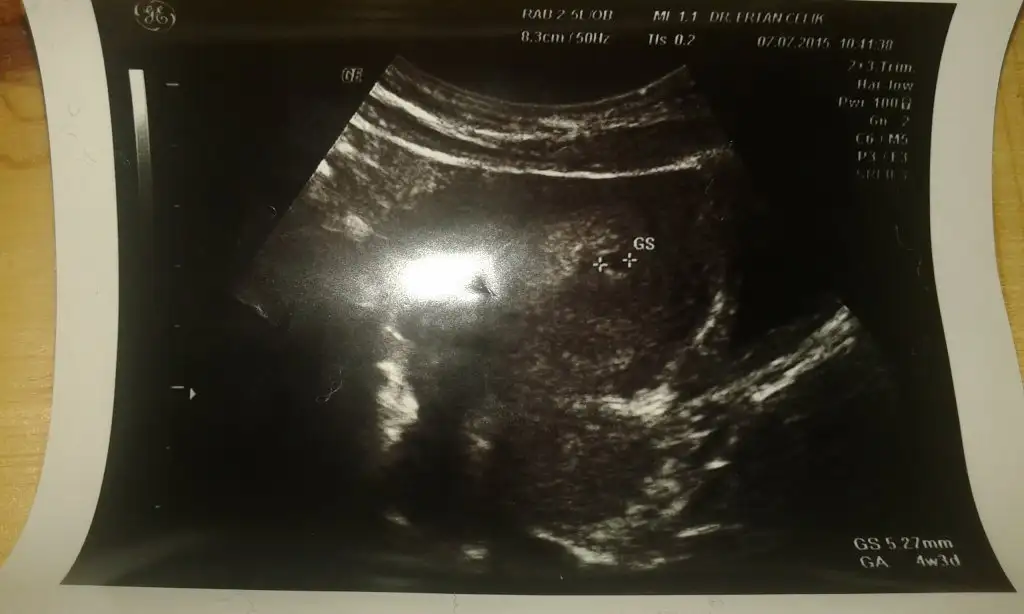

Canim sen 4+4 degilsindir benim 3+5ken degerim 852ydi keseyi goremedi 5 gun sonra gittim biraz gec gittim garanti keseyi goreyim diye 4+3de 5.27mm keseyi gorduk hcg yapmaya gerek duymadi doktor son adet tarihim 23 mayisti benim senin kacti tarihinCanım senin hcg kaç çıktı 4+3 ken ? Hemen görmüş keseyi ne güzel bana bi karartı var bu olabilir dedi ama görmediyrn yine gidicem

Bak ilk resmi ufak bi karalti iki + isaretinin arasinda insallah sende yarin gorursun minigi2gün oldu yrn yine çağırdı keseyi görene kadar gidip gelceksin dedi